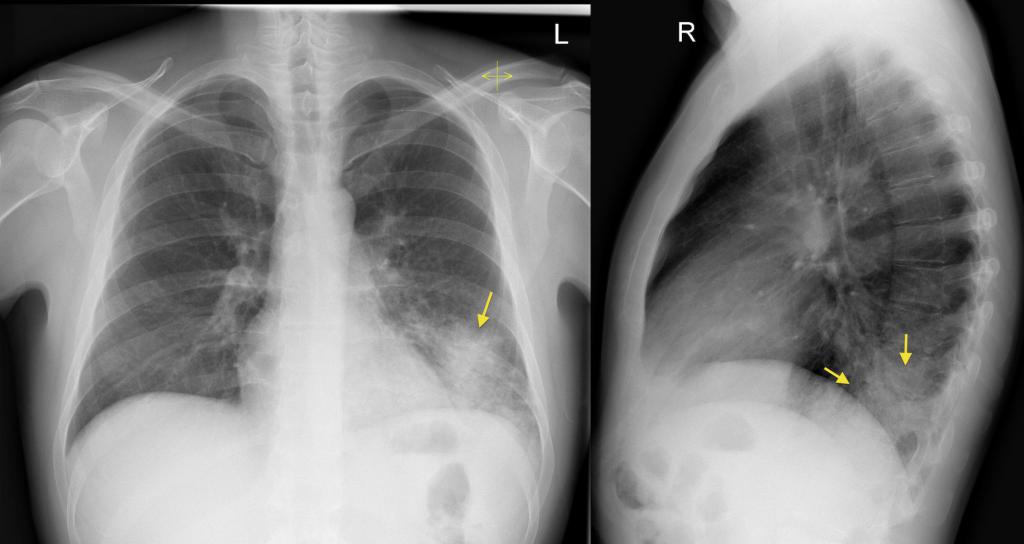

Как выглядит пневмония на снимке (рентгеновском), если она крупозного вида:

- субтотальные, тотальные затемнения с одного или же двух краев;

- смещение средостения в сторону предельного поражения;

- изменение физического поражения куполов диафрагмы;

- закупорка реберно-диафрагмальных синусов жидкостью;

- полное деформирование легочного рисунка;

- тяжистость корней легких.

Выявить особенности крупозного воспаления возможно на рентгенограмме. Однако при патологии медицинским стандартом диагностики считается рентгенография в двух проекциях (прямая и боковая). Такого рода список процедур совершают для оценки численности пораженных частей легких и исследования состояния средостения.